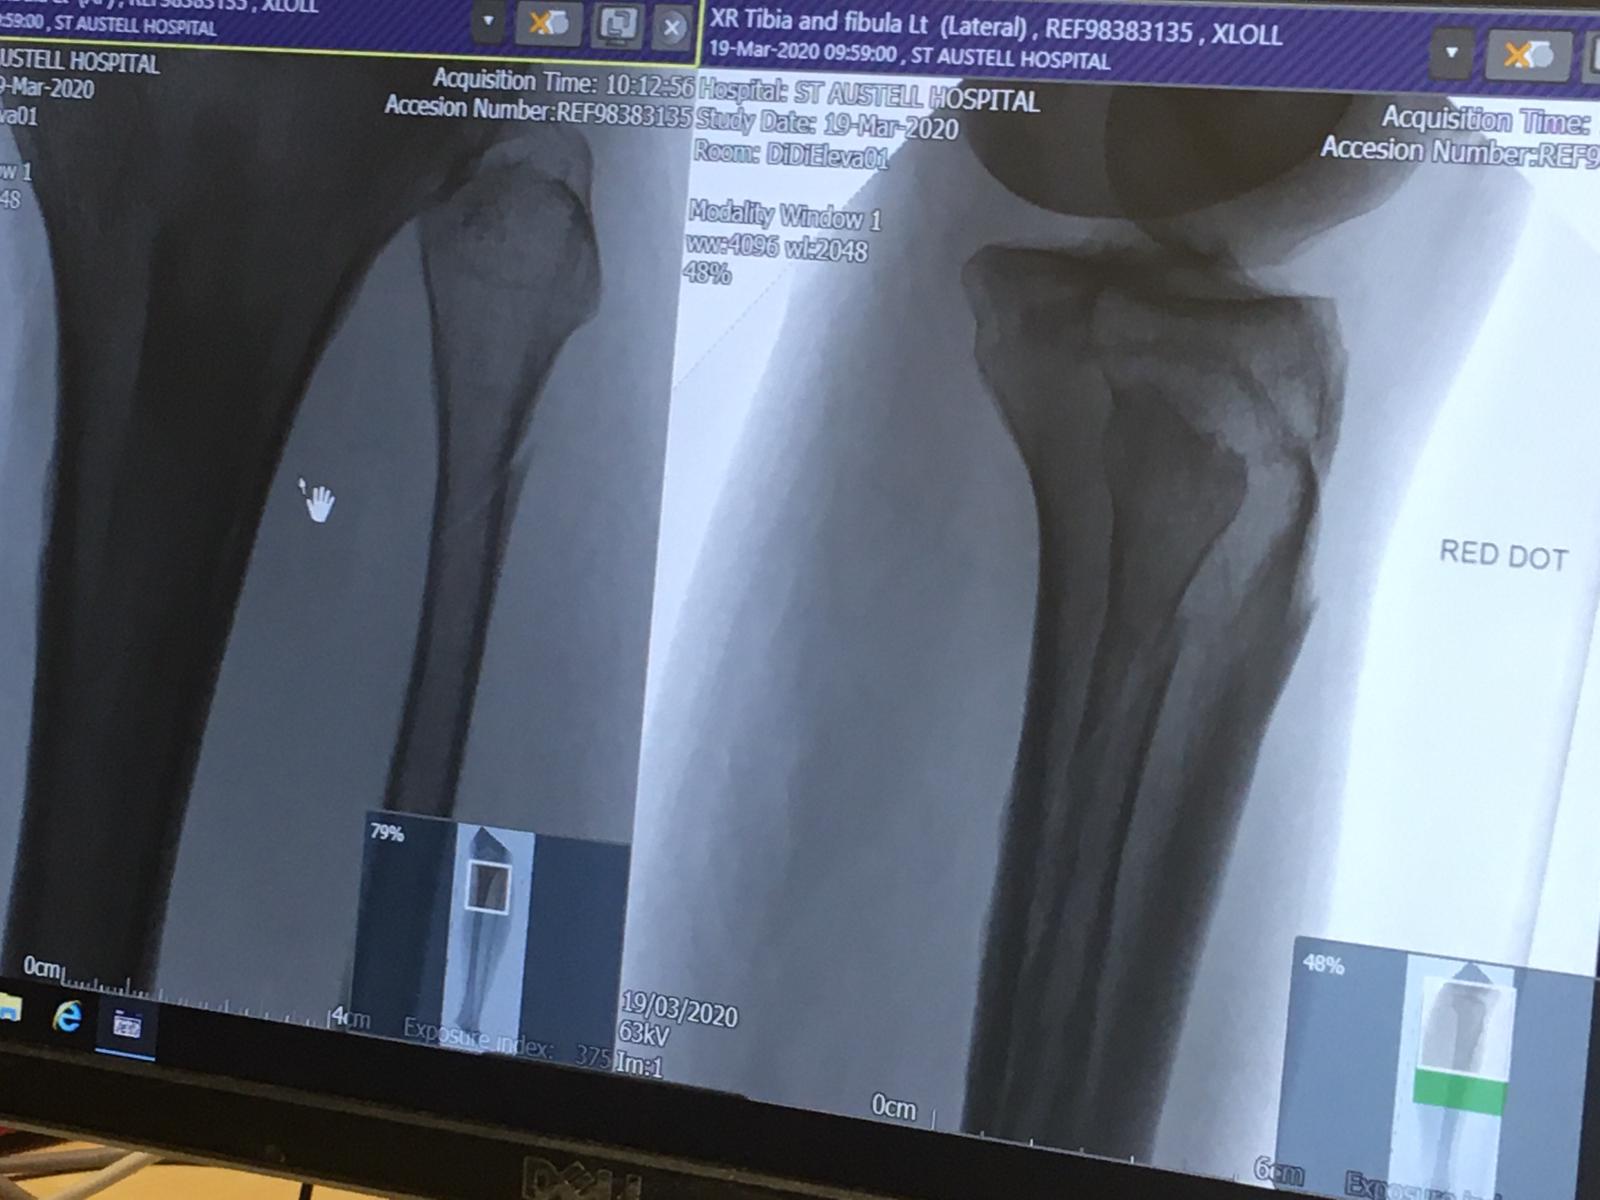

What an eventful shortened holiday the repercussions of which continued the next day with Graham going to St Austell Hospital for an X-rayed on his foot to discover it wasn’t a sprained ankle but a double fracture to his left leg, both tibia and fibula bones, just below the knee !